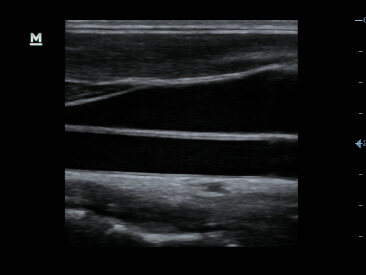

Im├Īgenes cl├Łnicas